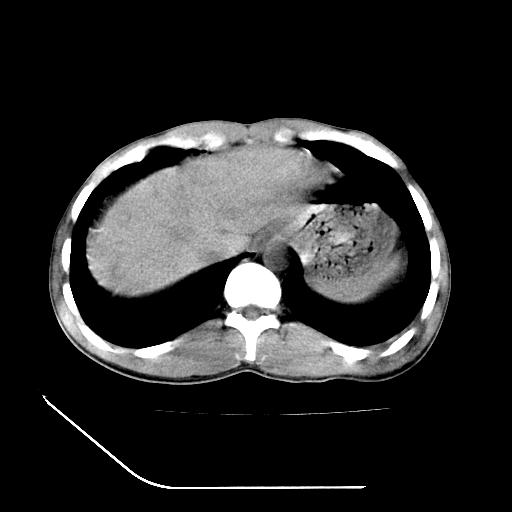

左肾挫裂伤并肾周血肿;

支持:1、左肾挫裂伤并肾周血肿;

2、少量腹水;

3、左肾旋转不良;

4、反射性肠淤张。

综上所述,考虑1:左肾挫伤并包膜下血肿2:少量腹腔积液3:肠梗阻的可能

除了1:左肾挫裂伤并肾周血肿;

2:少量腹水

第二次ct检查后:临床医生腹水穿刺后考虑肠系膜动脉破裂,后实行剖腹探查:于空肠距离十二指肠90cm处发现肠管破裂,破裂口较小;修补后关腹。